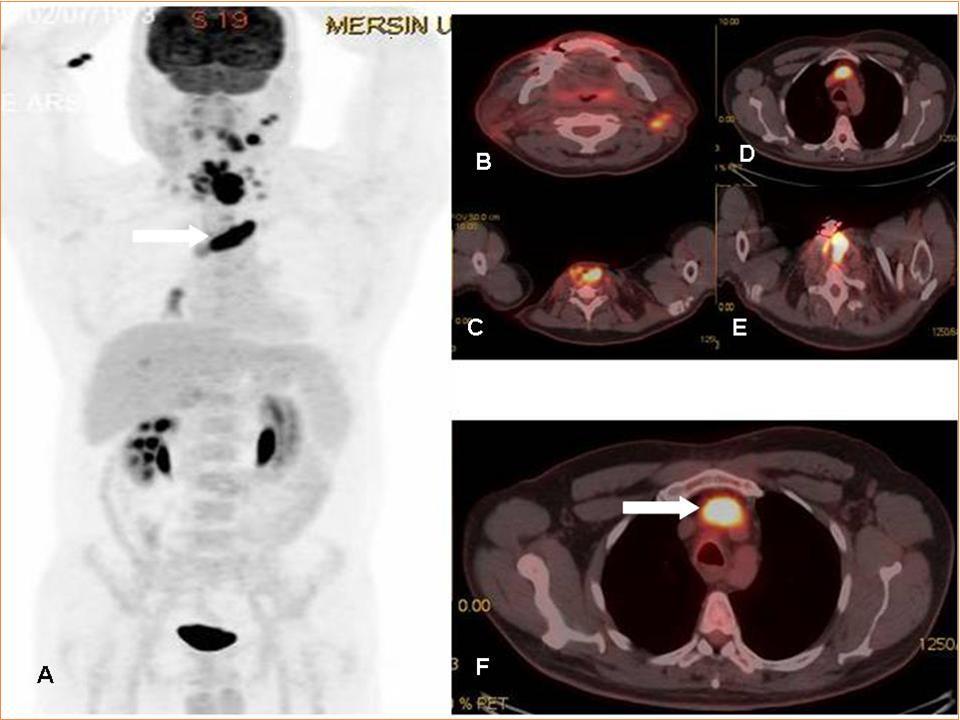

The incidence of thrombus is high in patients with underlying malignancy. This thrombus is mostly venous thromboembolism (VTE), but it may rarely be a tumor thrombus (TT). VTE is common in oncologic patients and is treated with anticoagulant treatment agents whereas aggressive treatment approaches are needed in TT. TT may occur in any cancer and has been reported in many different malignancies (ie, solid carcinomas, sarcomas, and hematologic malignancies) with RCC and HCC being considered the most common underlying malignancies1. In literature, there is only retrospective few articles and some case reports on the role of FDG PET-CT imaging 2, 3, 4, 5, 6. The FDG uptake pattern in TT is not yet as conclusively established, but generally, a linear FDG uptake pattern or more focal FDG accumulation has been reported in literature 2, 3, 4, 5, 6. In a recent interesting image report from Sonavane SN et al, the authors reported the imaging findings of a patient with RCC where PET/CT not only ruled out locoregional adenopathy and distant metastases, but also distinguished tumor thrombi from benign thrombi in the same patient 7. Incidental detection of secondary malignancies or occult metastases from primary malignant disease on 18F-FDG PET/CT has been reported previously 8, 9, 10. In this case report, FDG PET-CT imaging was very useful for diagnosis of tumor thrombus in a patient that diagnostic CT scan could not distinguish tumor thrombus & venous thrombus (Figure 1 A-F).

Figure 1.MIP (Maximum intensity Projection-A) and axial PET-CT fusion (B-F) images demonstrate recurrent mass lesion, metastatic lymphadenopaties and tumor thrombus (white arrows).

MIP (Maximum intensity Projection-A) and axial PET-CT fusion (B-F) images demonstrate recurrent mass lesion, metastatic lymphadenopaties and tumor thrombus (white arrows).